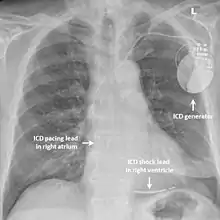

La quinidine prolonge l'intervalle QT et réduit la susceptibilité ventriculaire à un trouble rythmique[13],[14], et semble efficace dans la prévention de ces derniers[15]. Les antiarythmiques de la classe IC (dont flécaïne) ou III (amiodarone) n'ont pas prouvé d'efficacité[16]. La pose d'une défibrillateur automatique implantable peut être discuté. Le réglage de ce dernier reste délicat devant un nombre important de chocs inappropriés[3], et prône aux interférences avec l'onde T, plus ample[17].